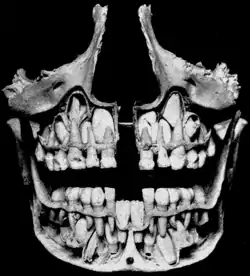

The removed bone reveals permanent teeth below the roots of primary teeth. | |